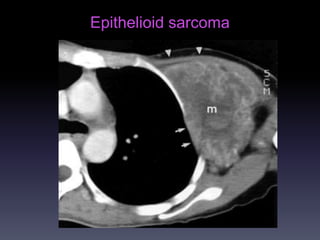

Epithelioid sarcoma

U XÖÔNG &PHAÀNMEÀM Hình CT -Huûy, bieán daïng xöông / Toån thöông phaàn meàm/ Xoùa lôùp môõ ngoøai maøng phoåi (+/- ) -Caàn khaûo saùt coù caûn quang. Vai troø CT -Ñaùnh giaù toát vò trí, möùc ñoä, lieân quan toån thöông vôùi caùc caáu truùc khaùc ngöïc (phoåi, maøng phoåi, trung thaát)